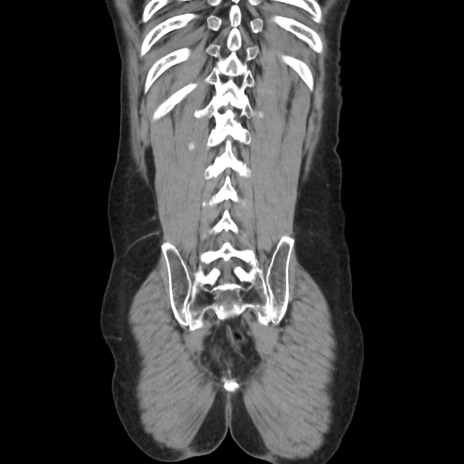

症例37(冠状断像)

【症例】40歳代 男性

【主訴】腹痛

【現病歴】4時間ほど前に電車に乗車中に臍部上より腹痛出現。徐々に増悪し起立困難となり、救急外来受診。生ものは数日食べていない。今朝お雑煮を食べた。

【身体所見】BT 36.8℃、BP 117/84mmHg、HR 91/min、SpO2 97%、苦悶様、腹部:臍上部広範囲圧痛あり、反跳痛±

【データ】WBC 8100、CRP 0.03